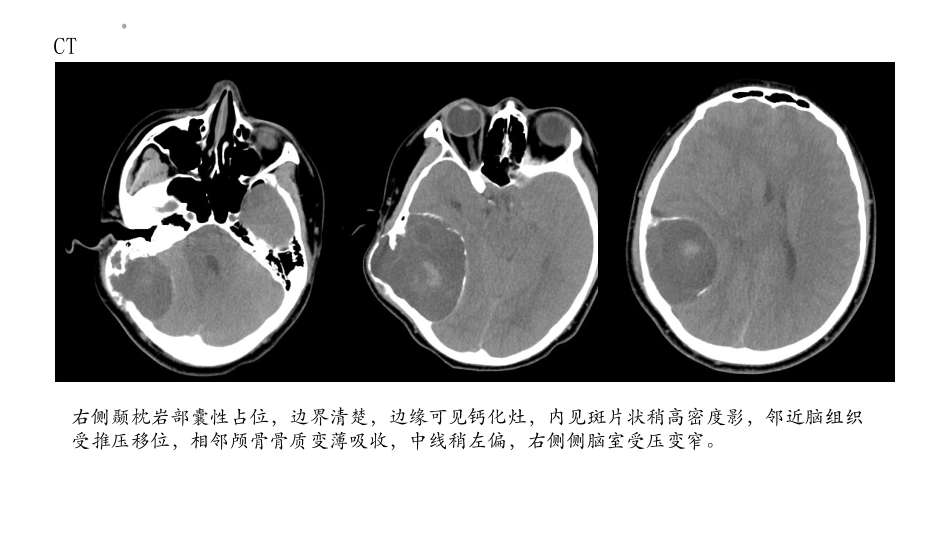

病例:男,15岁,于半年前无明显诱因出现右侧头痛,并发现右耳后方有一黄豆大小包块,并伴有压痛,在当地医院行包块穿刺考虑淋巴结炎,后行消炎治疗。右耳后方包块逐渐增大,现有鸡蛋大小,为求进一步诊治入院,头部CT平扫示右侧颞枕岩部多发囊性占位。CT右侧颞枕岩部囊性占位,边界清楚,边缘可见钙化灶,内见斑片状稍高密度影,邻近脑组织受推压移位,相邻颅骨骨质变薄吸收,中线稍左偏,右侧侧脑室受压变窄。MRI右侧颞枕岩部囊性占位,呈长T2信号影,内见分隔,边界清楚,内见斑片状等T2信号影,邻近脑组织受推压移位,中线稍左偏,右侧侧脑室受压变窄。MRI右侧颞枕岩部囊性占位,呈长T1信号影,内见分隔,边界清楚,内见斑片状等T1信号影,邻近脑组织受推压移位,中线稍左偏,右侧侧脑室受压变窄。MRI右侧颞枕岩部囊性占位,呈长FLAIR信号影,内见分隔,边界清楚,内见斑片状等低信号影。MRIDWI示占位示病灶内见小点状高信号影,ADC呈低信号影,余未见明显弥散受限区域。MRICE:病灶明显不均匀强化,内见片状无强化区。病理结果大体:灰白灰黄碎组织一堆,总体积9.5cmx8cmx1cm。镜下:于黏液水肿样的背景内见大量的泡沫样、含有脂质的组织细胞、纤维细胞及较多的淋巴细胞,纤维细胞异型性小,细胞呈短梭形,核分裂象罕见;局灶区域可见纤维细胞穿插侵及周围的骨组织;结合镜下形态及免疫组化结果,考虑为黄色肉芽肿,请结合临床资料及影像学检查除外其他纤维组织相关的疾病,或赴上级医院会诊。颅内黄色肉芽肿黄色肉芽肿(xanthogranuloma,JXG)是一种好发于皮肤和黏膜的少见的良性非朗格汉斯细胞组织细胞增生症(Langerhanscellhistiocytosis,LCH),发生于颅内者非常罕见。2016年,世界卫生组织(Wo_x0002_rldHealthOrganization,WHO)中枢神经系统肿瘤分类将其分在组织细胞肿瘤大类里。90%的患者只表现为头颈部区域皮肤病变,偶尔也累及多个组织器官,如眼睛、皮下软组织、肝、脾、肺、肾脏、骨骼和中枢神经系统(centralnervoussystem,CNS),单独发生于颅内者更罕见。颅内黄色肉芽肿肿块大体呈淡黄色,质韧,切面灰白、灰黄色,薄层包膜,血供丰富。肿瘤主要由较大的泡沫样组织细胞和少量的梭形组织细胞组成,散见淋巴细胞、浆细胞及嗜酸性细胞,且Touton多核巨细胞是本病特征。本病细胞的种类、数量和形态因病灶的分期不同而不同,越到晚期,成纤维细胞越多、纤维化越重。病灶间质常有黏液变性,局部血管丰富且伴出血。颅内黄色肉芽肿病灶脑外颅底多见,好发部位依次为鞍区、迈克尔腔、侧脑室、后颅窝及脑实质。边界多清楚,类圆形,大者边缘分叶状。病灶占位效应明显,周围脑实质常有水肿。CT平扫呈等或略高密度,增强扫描病灶明显均匀强化,临近颅骨有增生硬化或受压吸收变薄。MRI扫描T1WI信号均匀,多呈等信号,也可呈稍高、稍低信号,T2WI病灶多呈等、高不均匀信号,也有少部分病灶呈低信号或混杂信号;FLAIR、DWI均呈稍高信号。增强扫描呈均匀一致明显强化,主要是血管丰富及组织间隙较宽。感谢第一PPT